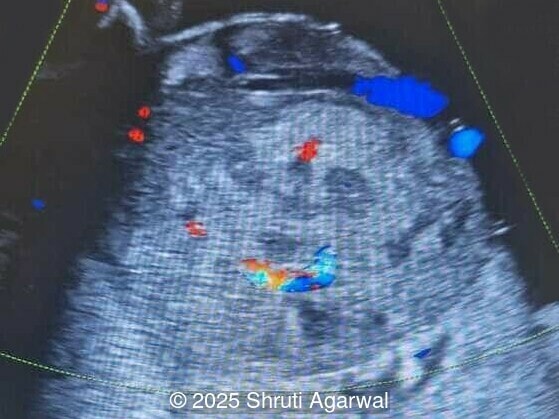

We present a case of fetal anemia due to a giant chorangioma.

• Image 4: pericardial effusion

Chorangiomas greater than 5cm are referred to as a giant chorangioma and occur in approximately 1 in 2,700 pregnancies [2]. Giant chorangioma can be clinically significant, causing various fetomaternal complications. In a study reviewing 175 cases of chorangioma, approximately 34% of giant chorangiomas experienced complications [2]. Arteriovenous shunting in giant chorangioma can increase venous return to the fetal heart, causing hypervolemia, tachycardia, and cardiomegaly, leading to heart failure, hydrops fetalis, and fetal demise. Large lesions can also divert nutrients and oxygen from the fetus, manifesting as growth restriction. Placentomegaly occurs due to a hyperdynamic circulation as a result of arteriovenous shunting.  In such cases, fetus may suffer from anemia and thrombocytopenia due to sequestration of red blood cells and platelets by the tumor. Polyhydramnios can occur due to both direct transudation into the amniotic fluid and to fetal polyuria secondary to the hyperdynamic circulation. Additionally, preterm delivery and maternal mirror syndrome with generalized fluid overload and preeclampsia can occur with giant chorangiomas [2,8].

Prenatal diagnosis depends on ultrasound, however, chorangioma can cause an increase in maternal serum alpha-fetoprotein [3]. Ultrasound examination reveals a hypo- or hyperechoic, well-circumscribed mass, which is usually located underneath the chorionic plate near the umbilical cord insertion, and often protrudes into the amniotic cavity. Color Doppler demonstrates large vascular channels around and within the tumor [6,9]. In cases of giant chorangiomas, echocardiography should be performed to assess cardiac function and measure fetal middle cerebral artery peak systolic velocity for diagnosis of fetal anemia. Regular ultrasounds with Doppler studies are used to monitor tumor size, fetal growth, amniotic fluid volume, and signs of fetal anemia or heart failure. The frequency of exams is based on tumor size and associated complications. With small tumors, assessment may occur every 3-4 weeks, whereas in large tumors, the ultrasound scan may be done every 1-2 weeks [3]. These regular assessments can diagnose conditions that require intervention, such as polyhydramnios, hydrops, or hemolytic anemia.